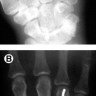

Upload Date: March 31, 2019 Full Size Image Dimensions: 313 × 941 Image Parent Post: Κατάγματα άνω άκρου

8b.Διαδερμική οστεοσύνθεση κατάγματος μετακαρπίου